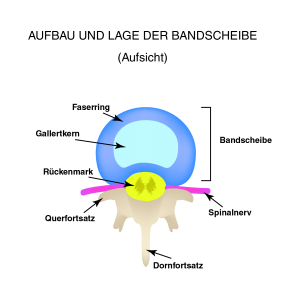

:background_color(FFFFFF):format(jpeg)/images/article/de/wirbelsaule/a1wjCWbEAeBhCqqodBbjHQ_Wirbels_ule_von_dorsal.png)